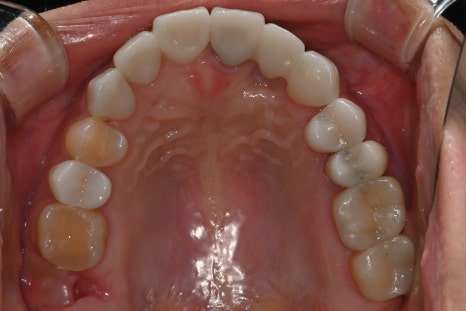

Right photo: “This is the inside view of the upper teeth after treatment. The color, curve, and position of the prosthetics were carefully matched and restored to look like natural teeth.”

to create a highly refined front tooth line with no sense of foreignness, like natural teeth.

This prosthetic work was custom-designed with the patient’s face shape, smile habits, and gum condition in mind,